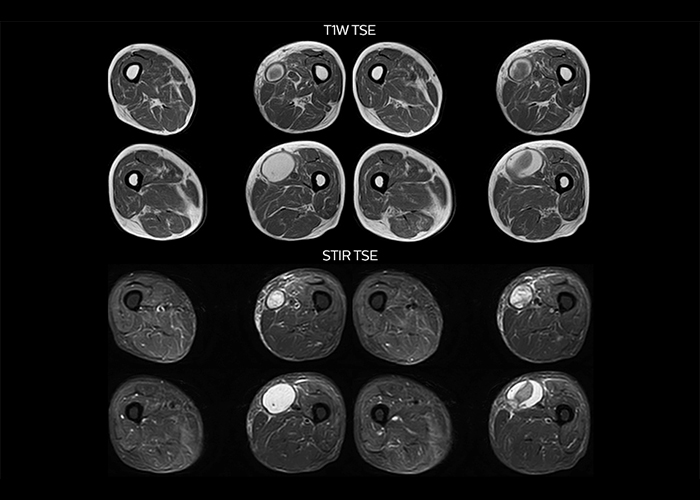

“To avoid coil changes we plan examinations of similar anatomies back to back, such as head and spine. Multiva helps us here a lot because coils don’t need to be changed frequently. Moreover, thanks to parallel imaging technology and 16-channel HeadSpineTorso and 8-channel MSK coils we are able to achieve excellent image quality. In this way Multiva helped us to increase both image quality and productivity.”

“Neurological cases, such as brain and spine imaging, represent the largest share in our MR scanning, followed by musculoskeletal cases. In general, we use simple and basic imaging protocols. But occasionally, we use advanced techniques for problematic cases if necessary.